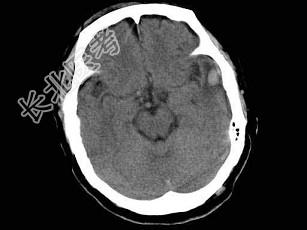

- 男,38岁, 外伤后半个月,行CT复查如